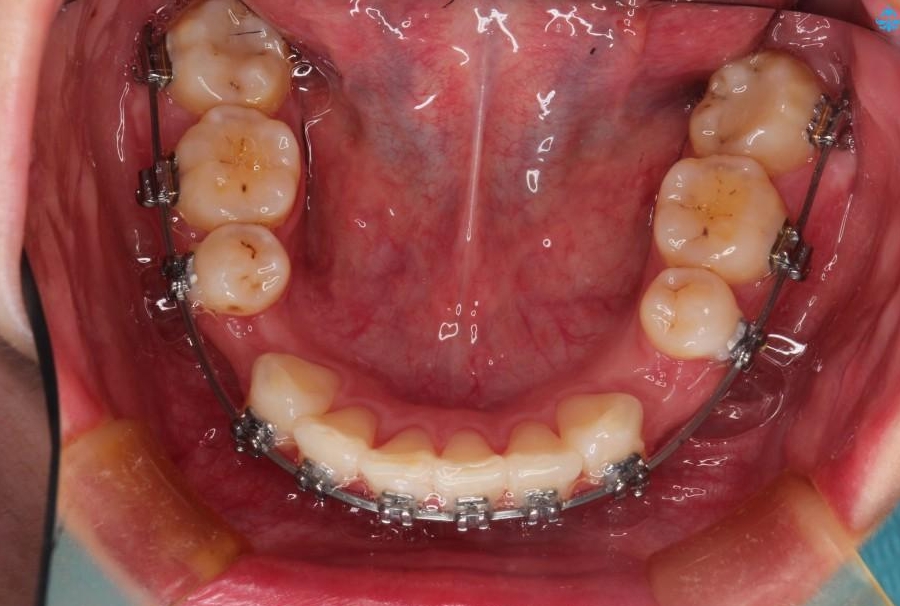

【20代女性】出っ歯の矯正 治療例

出ている歯を引っ込めるためのスペースを作るため、上下左右の小臼歯を抜歯し、ワイヤー矯正を行いました。治療後は、口元がスッキリとしたことで患者様にも喜んでいいただきました。

- 治療期間:2年

- 矯正装置:メタル装置